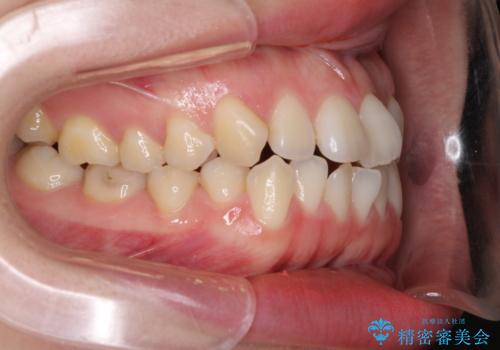

前歯のデコボコを治したい ワイヤー矯正

- 前歯のデコボコが気になるとのことで来院された患者様です。

1年半程度の期間を見込んでいましたが、上下の真ん中の位置をできる限り合わせるための調整に少し時間がかかってしまいました。

咬み合わせが安定し、前歯の汚れも付きにくくなりました。